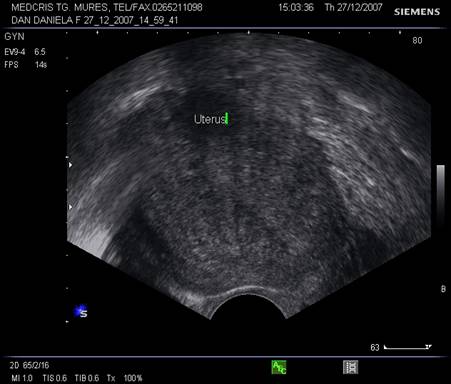

Uterul - situat intre vezica si rect, pozitia lui poate fi variabila, influentata si de umplerea vezici. De obicei, corpul uterin si colul au o relativa omogenitate interna ecografica. Cateodata imagini anecogene in peretele cervical reprezinta chiste Naboth.

Dimensiunile uterului la o pacienta nulipara matura, masurate transvaginal sunt de 7,3 cm x 4,0 cm x 3,2 cm. In general dimensiunile cresc cu paritatea si scad dupa menopauza.

Raportul intre corp si col este aproximativ de 1,6 in ceea ce priveste lungimea.[5,6]